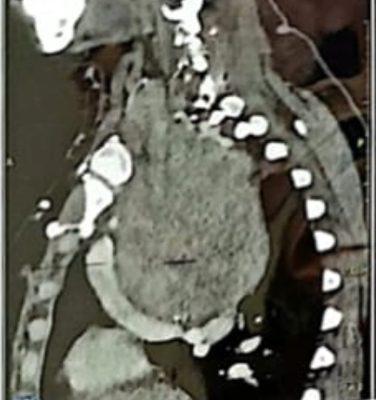

في إطار النجاحات المتواصلة التي تحققها جامعة كفر الشيخ في المجال الطبي، نجح فريق طبي متخصص من قسمي جراحة الرأس والرقبة وجراحة القلب والصدر بمستشفى كفر الشيخ الجامعي، في إجراء عملية جراحية دقيقة ومعقدة لمريضة في العقد الخامس من عمرها، كانت تعاني من صعوبات تنفس شديدة، نتيجة وجود ورم ضخم بالغدة الدرقية داخل التجويف الصدري، ضاغطًا على الوريد الأجوف العلوي (Totally intrathoracic retrosternal goitre compressing the superior vena cava).

الجدير بالذكر أن هذه الجراحة قد استغرقت نحو أربع ساعات، أجريت باستخدام أحدث الأجهزة والتقنيات الطبية المتقدمة، وخرجت المريضة من غرفة العمليات في حالة صحية مستقرة وتخضع حاليًا للرعاية الطبية بالمستشفى الجامعي.